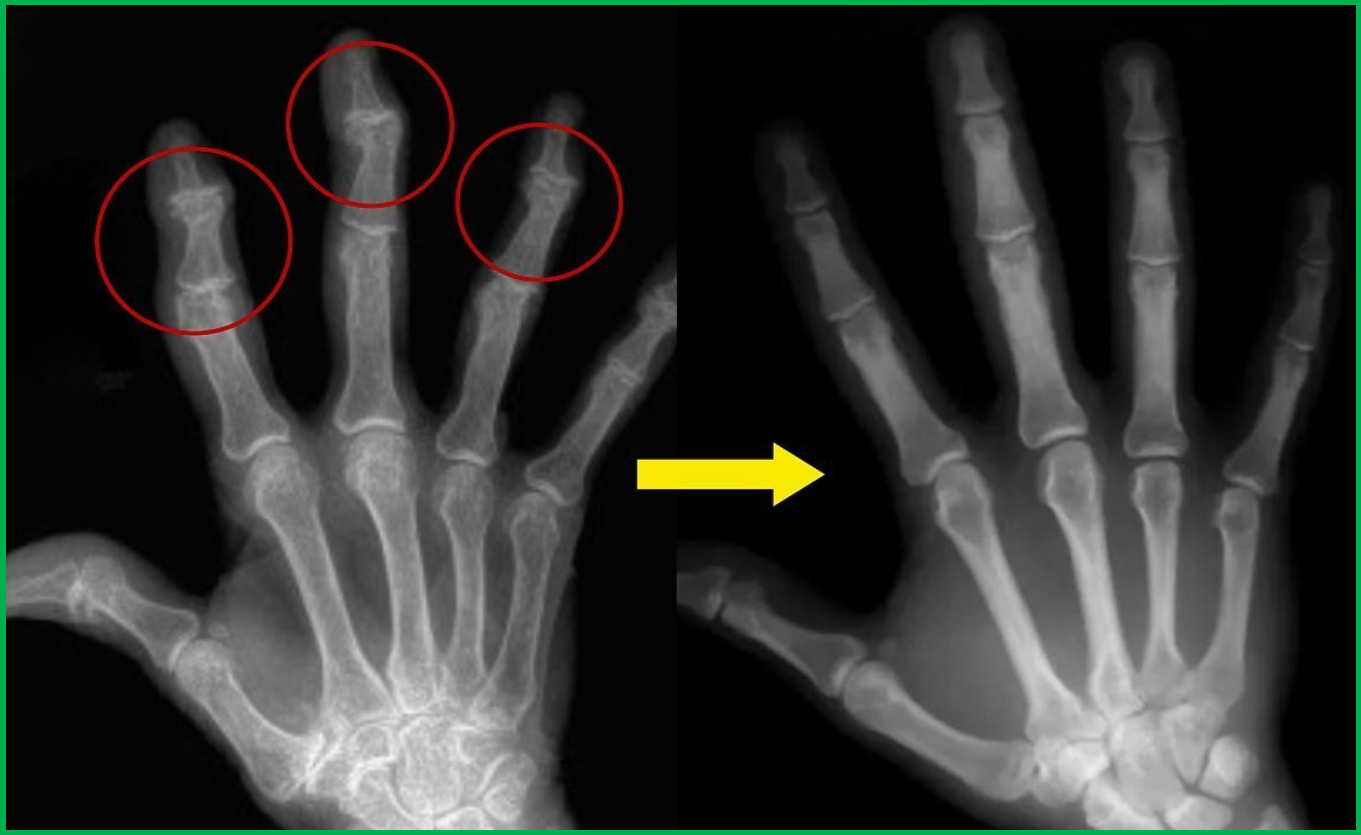

퇴행성 관절염, 또는 골관절염(Osteoarthritis)은 관절의 연골이 점차적으로 손상되면서 발생하는 만성 질환이다. 손가락 퇴행성 관절염은 손가락 관절의 연골이 닳아 없어지고, 이로 인해 뼈가 서로 마찰되면서 통증, 부종, 관절의 경직 및 변형을 초래한다. 초기에는 통증이 미미하지만, 병이 진행됨에 따라 손가락의 움직임이 제한되고, 손가락이 굳어지는 증상이 나타날 수 있다.

- 변형: 관절이 붓고 딱딱해지면서 손가락이 변형되는 현상이 나타난다.